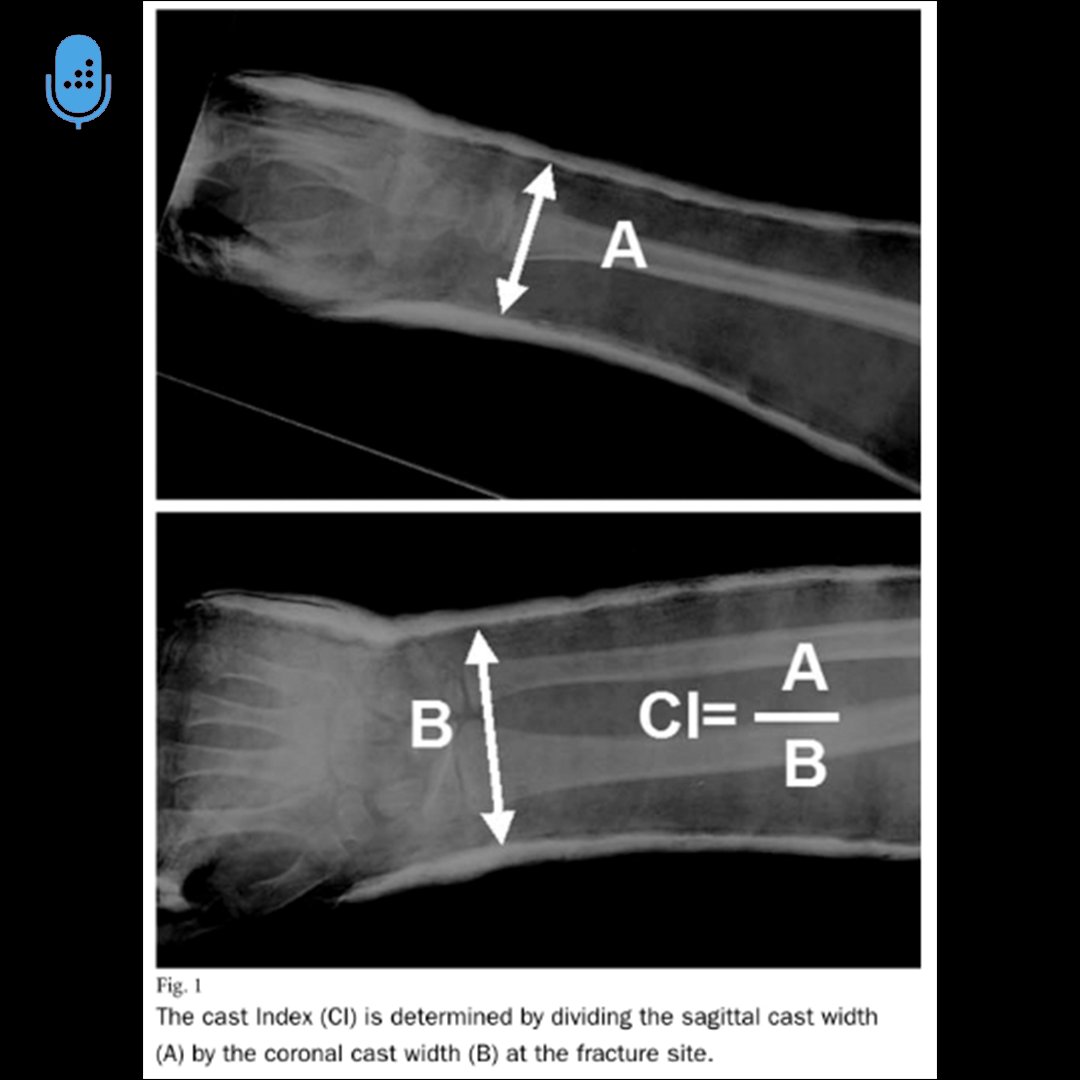

Can you answer this daily question from our Free QBank correctly?

QID: 215626